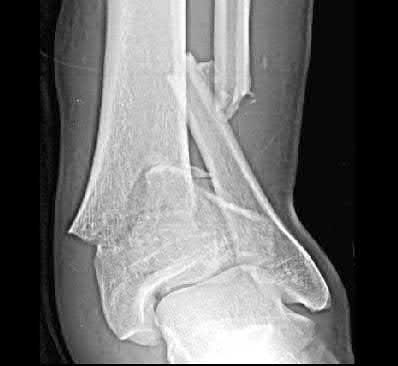

Figures A to C show radiographs of a 70 year-old male who fell on the ice 5 days ago. He could initially walk after the fall, but he is now unable to weight-bear on the leg due to pain. Physical examination shows diffuse ankle swelling, with no medial sided ankle tenderness. He is neurovascularly intact. The patient does not smoke and has no medical history. A gravity stress radiograph is demonstrated in Figure

D. After closed reduction, there is 2 mm of fracture displacement, no talar shift and the talocrural angle = 83 degrees. What is the most appropriate treatment?

Figure A demonstrates an AP radiograph of a Weber B fibula fracture with minimal medial clear space widening.

Figure B demonstrates a mortise radiograph of a Weber B fibula fracture with a congruent mortise.

Figure C demonstrates a lateral radiograph of a Weber B fibula fracture with a congruent mortise.

Figure D demonstrates a stress radiograph with minimal medial clear space widening.